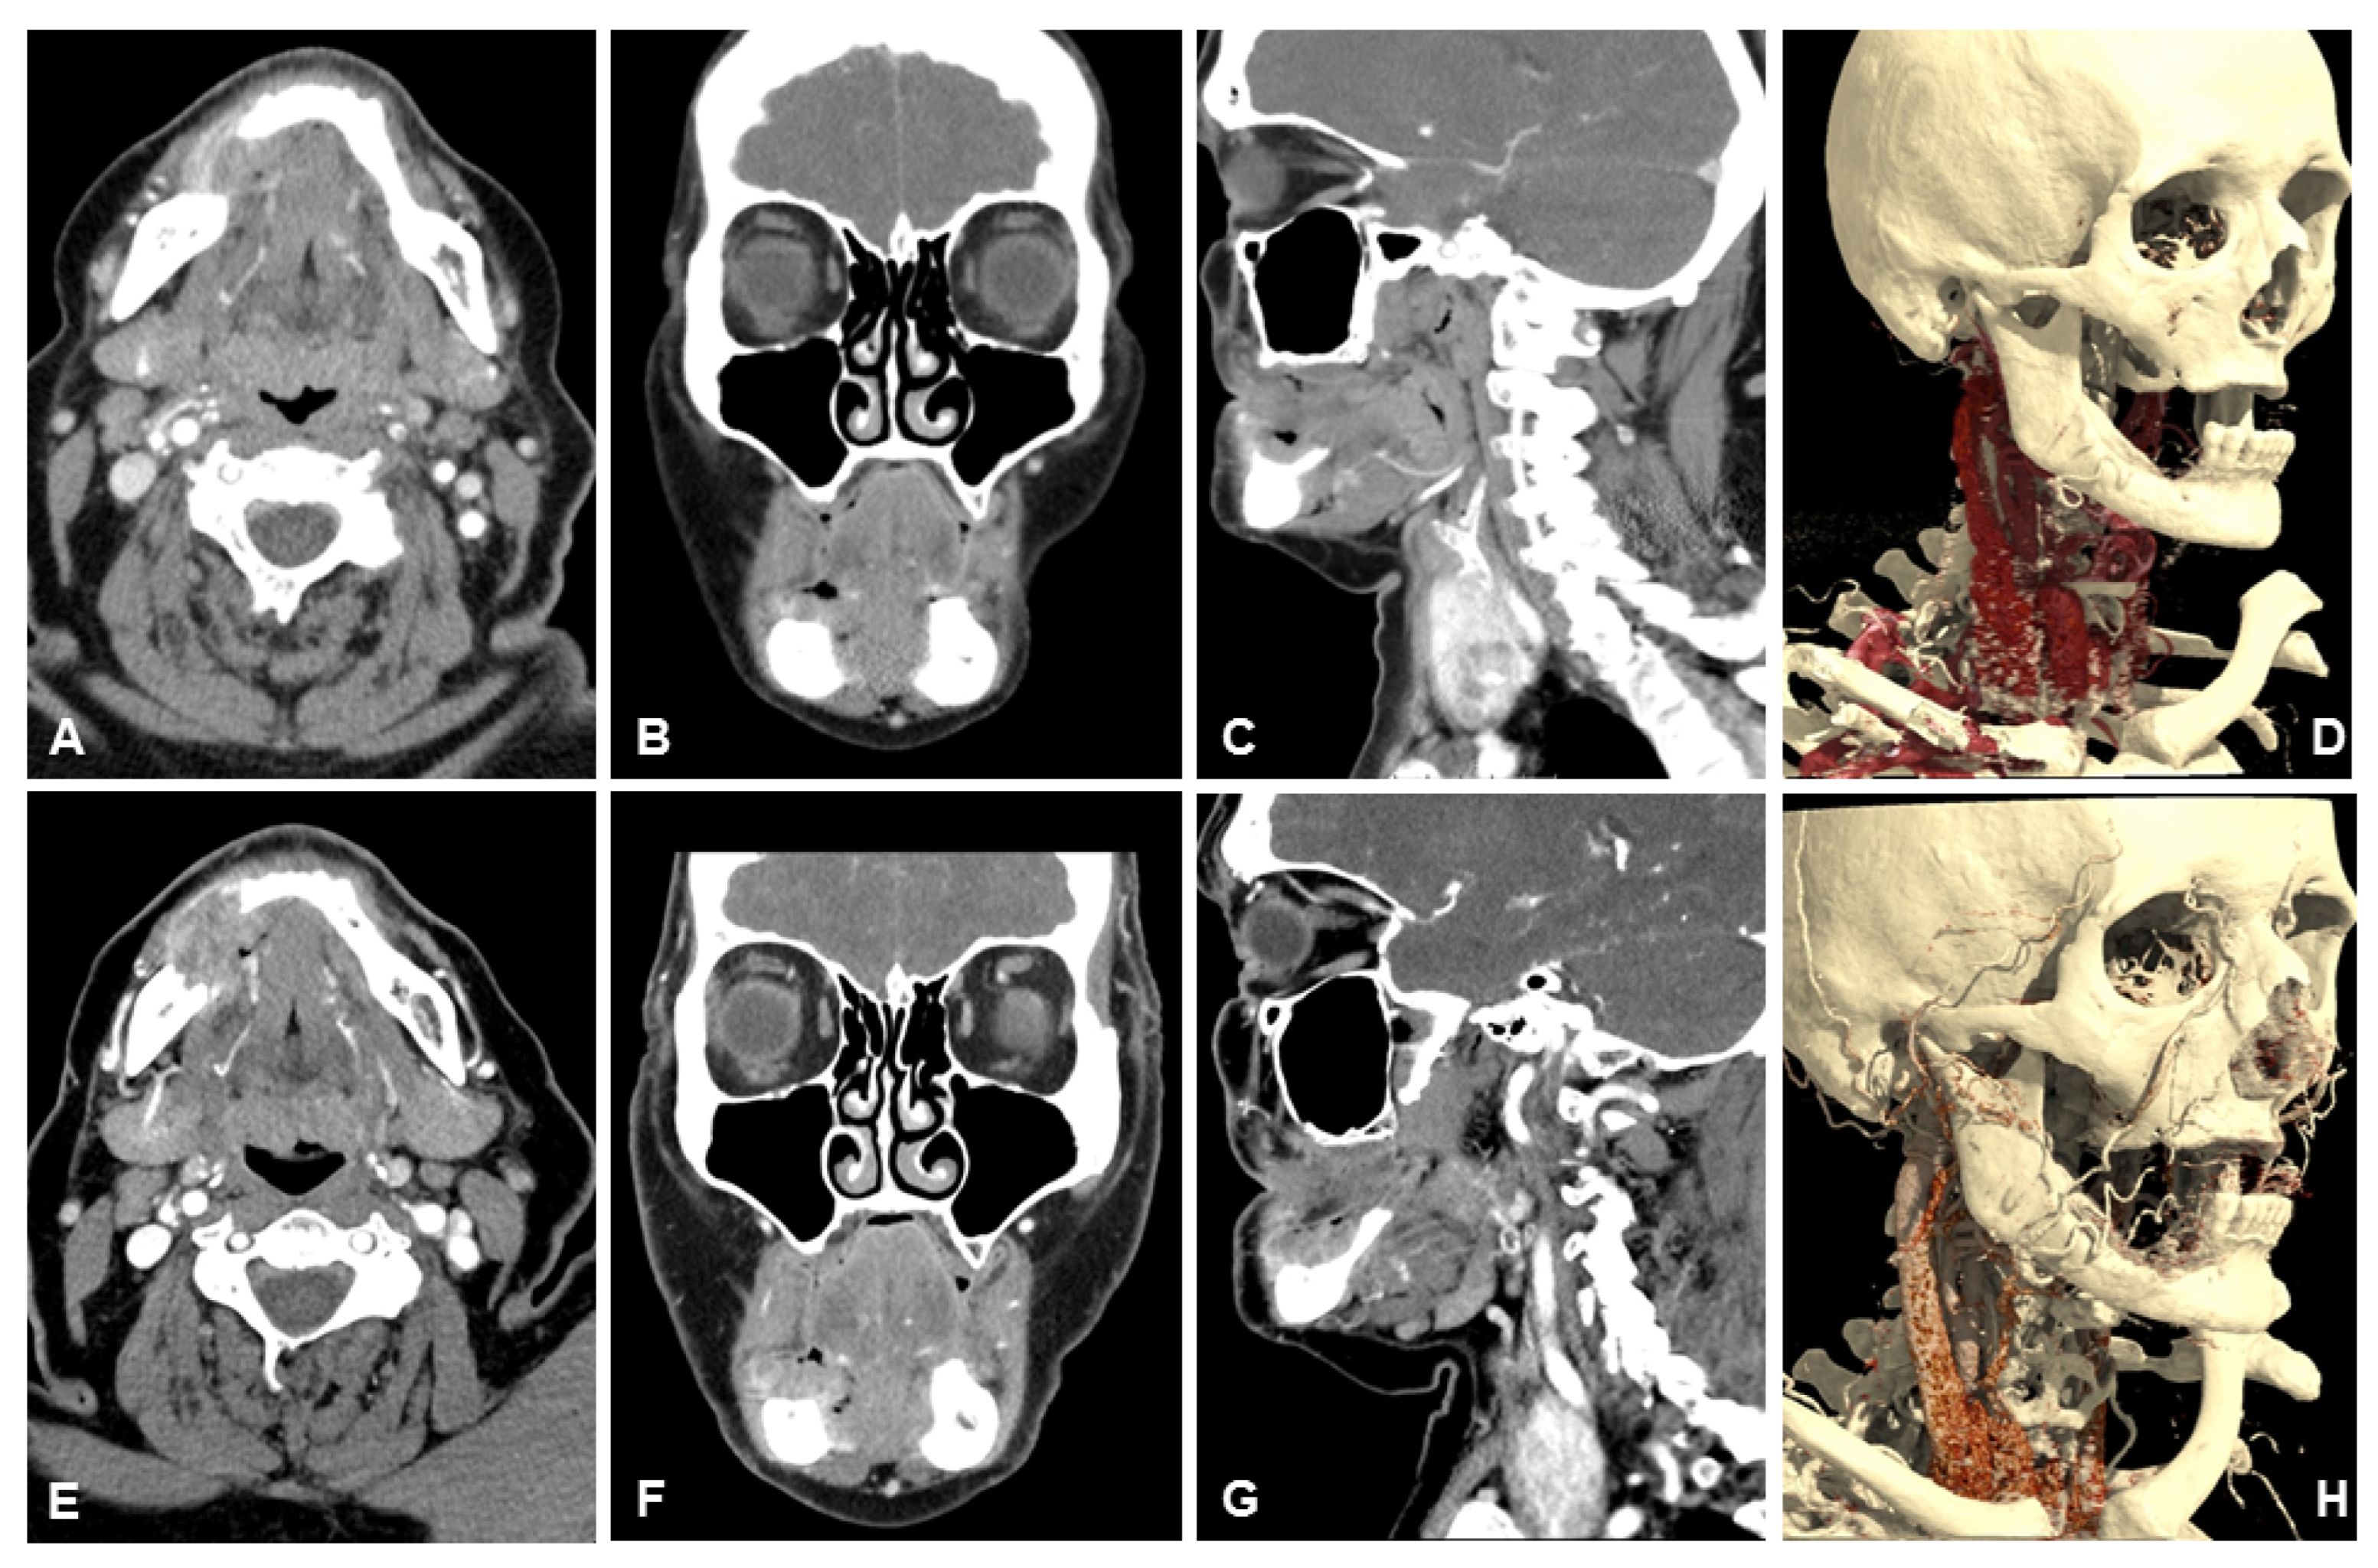

Table 3 lists the scores of both readers for subjective image quality in detail. Patient examples are given in Figure 4, Figure 5 and Figure 6.

Figure 6. Example of a 93-year-old female patient with a squamous cell carcinoma of the left cheek. UHR-CT enables an accurate identification of arterial supply and venous drainage of the neoplasm, which is clearly depicted with 3D-reconstruction. It is possible to precisely differentiate between perineural tumor spread (red arrow) and adjacent muscle. (A) axial 3 mm reconstruction UHR-CT, (B) coronal 3 mm reconstruction UHR-CT, (C) sagittal 3 mm reconstruction UHR-CT, (D) best possible 3D-reconstruction NR-CT.